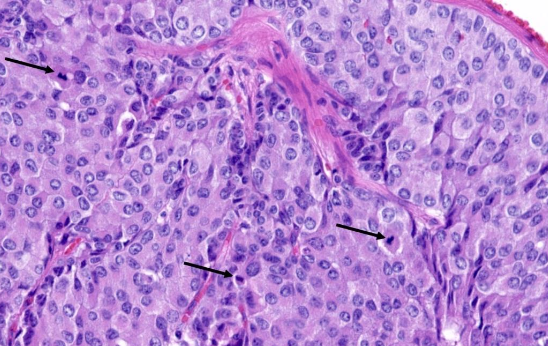

<p>EFECTO DE AZZOPARDI</p>

EFECTO DE AZZOPARDI

Tinción basofílica de las paredes vasculares debido a acumulación de ADN de núcleos necróticos